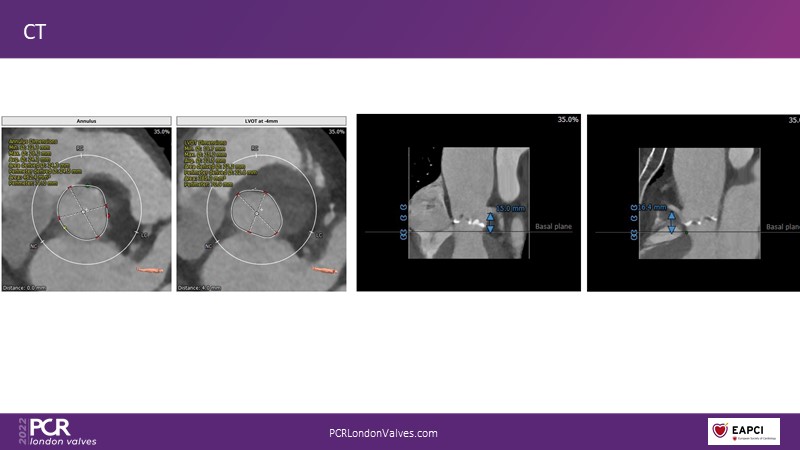

This session addresses three important topics that impact post-procedural and long-term outcomes after performing TAVI: the impact of permanent pacemaker rates and paravalvular leak, the importance of neo-commissural alignment, and the role of cerebral embolic protection.

- To appreciate the potential importance of neo-commissural alignment